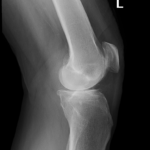

Your doctor will diagnose osteoarthritis based on the medical history, physical examination, and X-rays.

X-rays typically show a narrowing of the joint space in the arthritic knee.